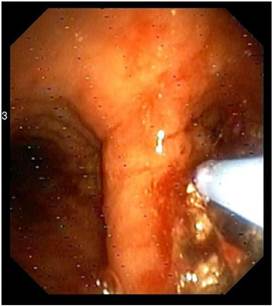

Figure 5

Cryoprobe performing debulking of central airways malignnat tumor.

J Cancer Image

Recent ACCP Lung Cancer Guidelines mention several interventional bronchoscopic modalities for palliation of dyspnea due to inoperable malignant CAO.[28] The results of the present prospective, controlled study confirm the considerable benefit of interventional bronchoscopic management of such patients and make an argument that patients with malignant CAO treated endoscopically have less dyspnea, better QoL, improved physical function and longer survival than patients with oncologic treatment alone. Combined interventional and oncologic treatment should be considered in any multidisciplinary cancer care program and offered to all patients with lung cancer and inoperable CAO, especially when post-obstructive atelectasis is present. Since such an approach is often limited by the lack of interventional equipment and skills, the urgent need for respiratory physicians' training in therapeutic bronchoscopy and development of interventional units is also highlighted.[29] (Figures 3-8) Additional treatment with radiotherapy could be used based on the patient performance status and local interventional prior or after stent placement-debulking.[30-36] Multimodality treatment is necessary for patients with central tumors local treatment should be accompanied with systematic treatment when possible.